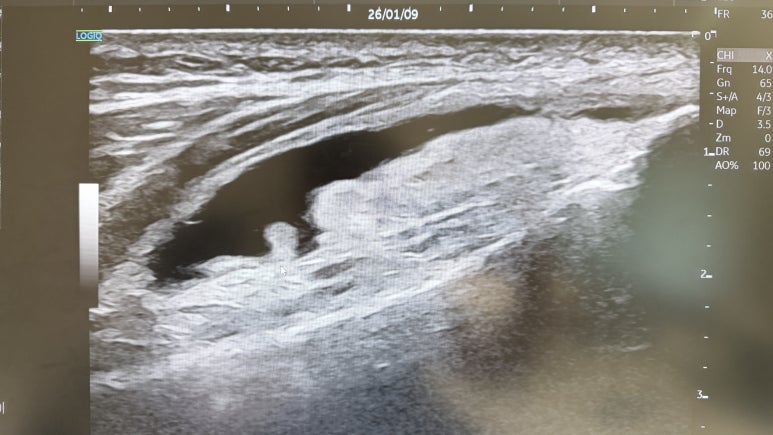

우리 한의학에서는 초음파를 보면서

문제가 있는 혈자리에서

'염증 유착 부위'를 찾아 정밀 치료합니다.

무릎 관절염 환자분들,

무릎 앞쪽에 쏙 들어가는 두 구멍 아시죠?

한의학에서는 '독비(ST35)'라고 부르는

아주 중요한 혈자리입니다.

경혈 초음파로 이 부위를 보면,

무릎 관절강과 연결된 '관절낭(Joint recess)'이

바로 보입니다.

염증이 가장 많이 고여 있고,

통증을 느끼는 신경이 예민해져 있는 곳이죠.

손으로 혈자리를 찾고

다시 한번 초음파로 확인하고

문제가 있는 깊이에 '힐트레이저"치료를 하는거죠.